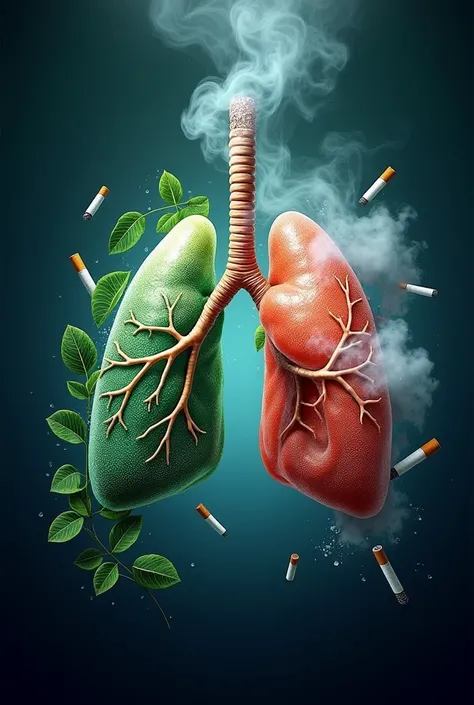

Generate a lungs, the right side lungs is healthy vibrant color surrounded with

Generate a lungs, the right side lungs is healthy vibrant color surrounded with fresh air. On the left side make the lungs damage or pollution of elements in smoking. Add some symbols of no smoking in the pulution part, and add some clean air in the right side lungs

Generate a lungs

the right side lungs is healthy vibrant color surrounded with fresh air

On the left side make the lungs damage or pollution of elements in smoking

Add some symbols of no smoking in the pulution part

and add some clean air in the right side lungs